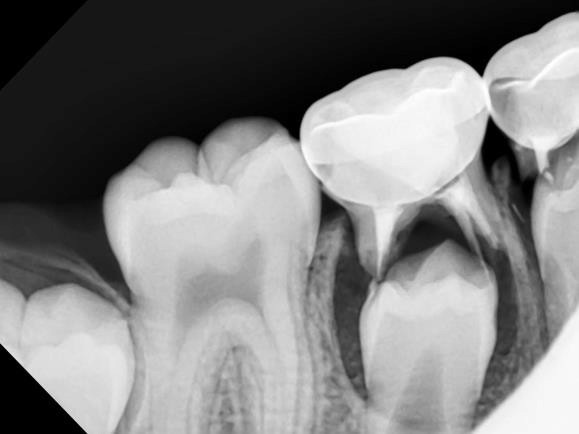

2. Cavities:

Tooth decay is caused by bacterial excretions that erode your enamel, and it can lead to tooth loss and treatments like dental crowns. It’s generally associated with poor diet and oral hygiene, but scientists have shown that it could also occur due to genetic susceptibility to the bacteria in your mouth. Family history and genetic testing can determine your risk for tooth decay, and preventive measures like sealants, fluoride treatments, and rigorous oral health can minimize the risk.

If your family history includes the need for orthodontic solutions or impacted wisdom tooth removal services, chances are that you will need them, too. X-rays or digital imaging can determine the positioning of wisdom teeth and the likelihood of issues coming up, while braces will help correct misaligned teeth.